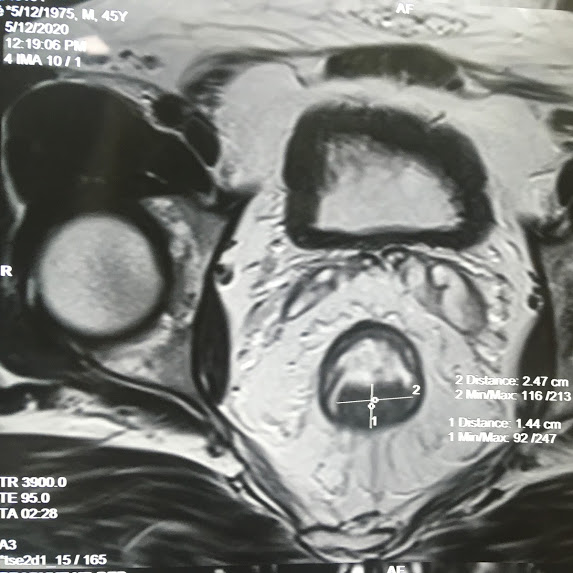

Covid Diaries: Successful laparoscopic removal of a distal rectal cancer in a patient. Laparoscopic surgery leads to faster recovery for the patient with less pain and good oncologic outcomes. with newer advances in mutlimodality treatmentand techniques ) (laparoscopy, stapling devices and expertise in intersphincteric resection) we are able to preserve sphincteric function in most patients with good oncologic and functional outcomes. We are continuing laparoscopic cancer surgery following all precautions in light of corona virus pandemic. Cancer treatment can't wait! online consultations also available.